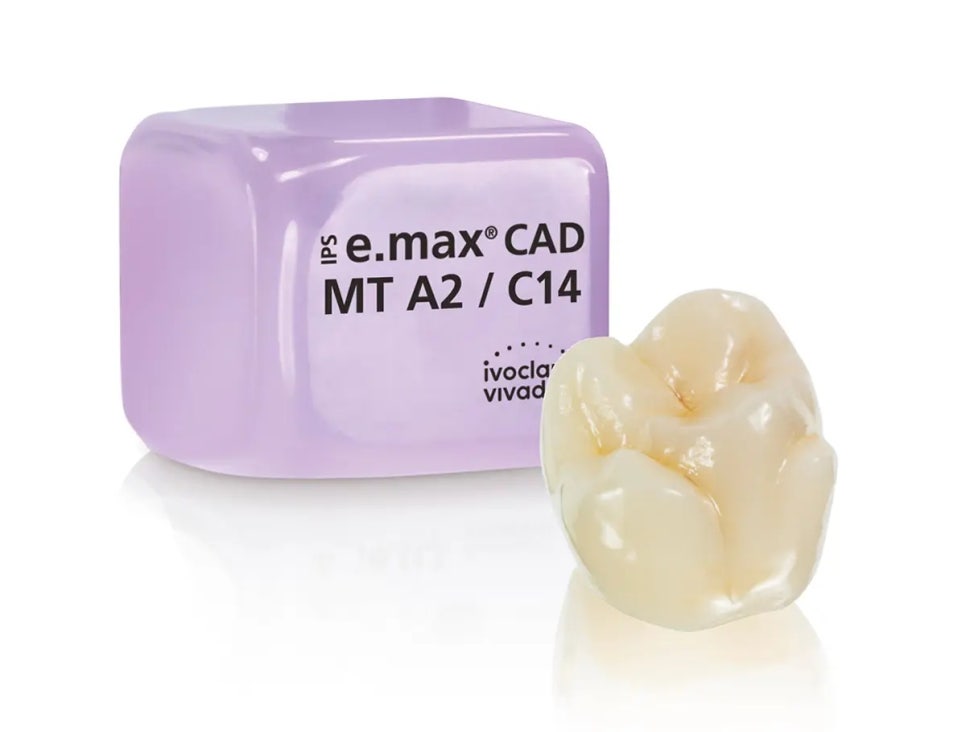

8) Is Lithium Disilicate (e.max) a “Premium” Material?

Lithium disilicate (often known by the brand e.max) is frequently used for veneers. The article explains why MINISH does not use this material, citing two concerns:

- shrinkage risk due to high-temperature heat treatment, which may contribute to gaps over time

- high hardness/wear resistance compared to natural teeth, potentially increasing wear on the opposing teeth (especially in patients who clench or grind)

9) Is Harder Always Better in Dental Materials?

Not necessarily. Ideally, restorative materials should behave similarly to natural teeth in:

- strength and hardness

- thermal expansion

- wear characteristics

- translucency and esthetics

Very hard ceramics (including zirconia and lithium disilicate) can be extremely durable—but because they’re harder than enamel, they may contribute to wear on the opposing natural teeth over time.

MINISH blocks are described as being engineered to more closely match natural tooth properties.